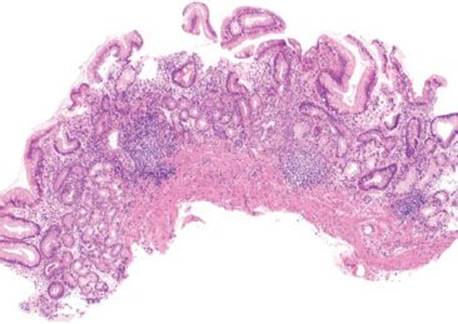

Lymphoid aggregates subpattern is defined as the presence of benign lymphoid aggregates or lymphoid follicles involving the mucosa (Figs. 2.114–2.119). This subpattern is perhaps the least specific of the chronic gastritis subpatterns, but one of the most common, and most easily identifiable at low power. Lymphoid aggregates can be seen in any form of chronic gastritis, regardless of etiology, and are commonly associated with EMAG’s Helicobacterinfection and treated Helicobacter. These aggregates can be antral predominant, or extend into the gastric body and fundus in EMAG.

Figure 2.116 Chronic gastritis pattern, lymphoid aggregate subpattern, AMAG. At scanning magnification, a prominent lymphoid aggregate is present in this body biopsy. Given the location of injury and the combination of background intestinal metaplasia and the total lack of oxyntic glands, the etiology is likely AMAG.

Figure 2.117 Chronic gastritis pattern, lymphoid aggregate, AMAG. Another example of prominent lymphoid aggregates at scanning magnification. Although this biopsy is labeled “body”, no oxyntic glands are present.

Figure 2.119 Chronic gastritis pattern, lymphoid aggregate, AMAG. Higher magnification of previous figure reveals intestinal metaplasia (top bracket), pyloric metaplasia (lower bracket), and total atrophy of oxyntic glands. The findings are strongly suggestive of AMAG.